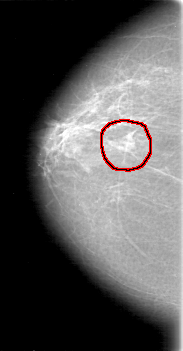

D_4081_1.RIGHT_MLO

RIGHT_CC LINES 5251 PIXELS_PER_LINE 2731 BITS_PER_PIXEL 12 RESOLUTION 43.5 OVERLAY

FILE: D_4081_1.RIGHT_MLO.OVERLAY

TOTAL_ABNORMALITIES 1

ABNORMALITY 1

LESION_TYPE MASS SHAPE IRREGULAR MARGINS OBSCURED

ASSESSMENT 0

SUBTLETY 5

PATHOLOGY BENIGN

TOTAL_OUTLINES 1

BOUNDARY